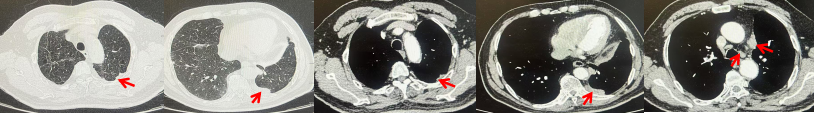

69岁男性,无糖尿病、高血压、心脏病等基础疾病,无吸烟、饮酒史,无肿瘤家族史。2023.06.07行胸部CT检查:右肺上叶胸膜下见肿物影,大小约33mm×22mm,边缘可见分叶,考虑恶性病变可能性大,双肺间质改变(如图1)。2023.06.14行“单孔胸腔镜下右肺上叶切除、肺门及纵隔淋巴结清扫、胸膜粘连松解术”;术后病理:(右肺上叶)腺癌(低分化,实体型占60%,不良腺体占40%),局灶伴神经内分泌标记表达(CD56、Syn),可见STAS及胸膜侵犯,未见确切神经侵犯及脉管内癌栓;(气管切缘)净;(淋巴结)未见转移癌0/26(2组0/2;4组0/6;7组0/2;对侧7组0/8;10组0/2;11组0/3;12组0/2;13组0/1)。术后分期pT2aN0M0 IB期,术后NGS基因检测:无驱动基因突变,PD-L1(22C3)TPS<1%。术后定期复查。

图1:患者手术前(2023.06)胸部CT肺窗及纵隔窗

图2:患者胸膜及肋骨转移(2024.11)胸部CT肺窗、纵隔窗及骨窗

图3:患者免疫联合化疗治疗后胸部CT,(A、B)图展示信迪利单抗联合培美曲塞+卡铂治疗

4周期(2025.02)疗效,(C、D)图展示信迪利单抗+培美曲塞维持治疗6周期(2025.07)疗效